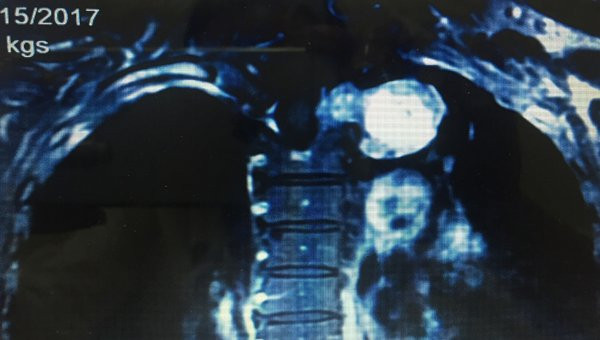

Khi chụp cộng hưởng từ, BS phát hiện có khối u từ trong ống sống ngực phát triển xâm lấn vào trong lồng ngực, khối u kích thước lớn 6x5cm.

| Hình ảnh khối u phình to trong tuỷ sống, chèn ép vào lồng ngực |

Khối u lớn ăn sát vào hõm đỉnh lồng ngực, đè đẩy vào bó mạch thần kinh cánh tay, đặc biệt là tĩnh mạch dưới đòn trái khiến bệnh nhân đau nhức. Bệnh nhân được chẩn đoán là u thần kinh tủy sống, chỉ định phẫu thuật.